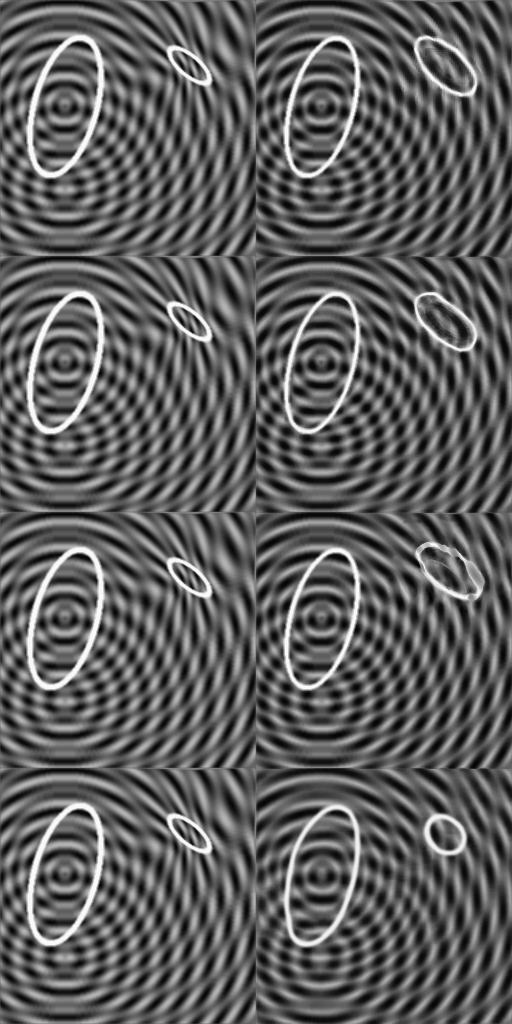

The purpose of weakly supervised algorithms is to overcome the need for pixel-wise labels and the human bias within these labels. In order not to be affected by this human bias, we designed a synthetic data set for the evaluation of our method. Two ellipses e1subscript𝑒1e_{1} and e2subscript𝑒2e_{2} are present in the image, one larger than the other and both with variable contour thickness, origin and orientation. The background is structured in concentric waves with two variable origins and variable wave length; this provides a higher level of complexity. Images of the healthy group \mathcal{H} keep this structure. If the image is deformed such that the smaller ellipse e1subscript𝑒1e_{1} shrinks to an even smaller ellipse, the background is also deformed. Images with this characteristics belong to the diseased group 𝒫𝒫\mathcal{P}. Implementation details are provided in the supplementary material.

In Figure 4, exemplary images of the two sets \mathcal{H} and 𝒫𝒫\mathcal{P} are shown. The pixel-wise ground truth (GT𝐺𝑇GT) is known by definition. We generate a training set of 2000 images of each class, and a validation and a test set with 200 images of each class.

Refer to caption(a)Refer to caption(b)Refer to caption(c)Refer to caption1-1

Figure 4: Images (a) and (b) show exemplary images of the sets \mathcal{H} and 𝒫𝒫\mathcal{P} respectively. Image (c) corresponds to the ground truth given by the difference (a) - (b).

In Figure 5, exemplary real images rp𝒫subscript𝑟𝑝𝒫{r_{p}\in\mathcal{P}} of the synthetic dataset with the corresponding artificial images ahsubscript𝑎{a_{h}\in\mathcal{H}} of the different methods are shown. Our method provides the most accurate difference map d𝑑d. The results of FP-GAN are good as well, but the method fails to generate a proper unshrunken ellipse e1subscript𝑒1e_{1}. VAE and VAGAN fail to generate an accurate image of class hh, resulting in a difference map not close to the ground truth. For visualization, we omit the StarGAN method since it is outperformed by its extension FP-GAN.

Refer to captionRefer to captionInput rpsubscript𝑟𝑝r_{p}Refer to captionRefer to captionOutput ahsubscript𝑎a_{h}Refer to caption11100|GT|𝐺𝑇|GT|Difference |d|𝑑|d|Input rpsubscript𝑟𝑝r_{p}Output ahsubscript𝑎a_{h}|GT|𝐺𝑇|GT|Difference |d|𝑑|d|DeScarGANFP-GANVAGANVAE

Figure 5: Visualization of the results of our DeScarGAN, FP-GAN, VAGAN and VAE for two samples of the synthetic dataset.